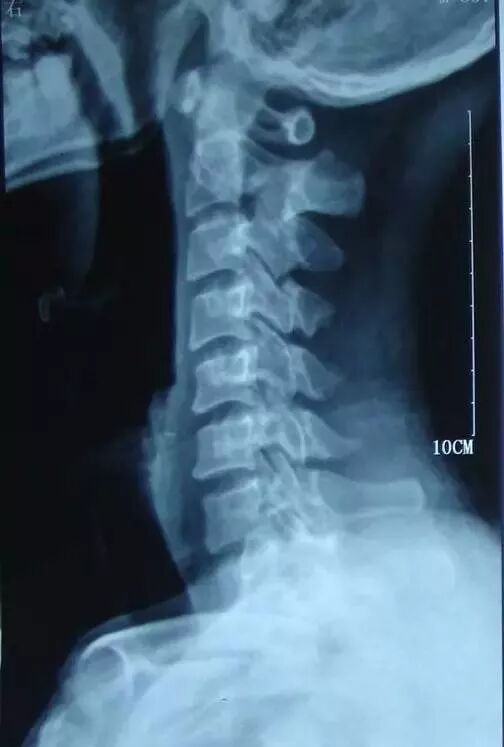

正常的颈椎呈“后伸”状态,以此缓冲头部的重力,同时,颈椎后方附着棘间韧带、棘上韧带、肌肉、筋膜等组织,以此维持颈椎的稳定性。

当办公一族及低头族长时间低头工作、追剧时,颈椎后方的韧带、肌肉、筋膜等软组织被牵拉,发生无菌性炎症,从而诱发颈部及颈肩部的僵硬、疼痛、活动不灵活等;长年累月的低头工作,颈椎的曲度会逐渐的变直,甚至呈现“前屈”的状态,颈椎间盘退变加剧,颈椎局部出现骨质增生,椎间孔变窄,严重者椎管变窄,脊髓受压,进一步引起一系列的神经系统症状,比如疼痛、麻木、走路不稳等等,这就是颈椎病的由来。

颈椎病的早期,患者会发现颈部发硬发僵,活动不灵活,颈部出现疼痛,可波及肩部;随着颈椎病的进展,颈椎神经收到压迫,患者会出现上肢的放射性疼痛、麻木,及波及双手,颈椎活动时,疼痛及麻木会加重,部分患者由于脊髓收到压迫,会出现走路不稳定,脚下有“踩棉花”的感觉。